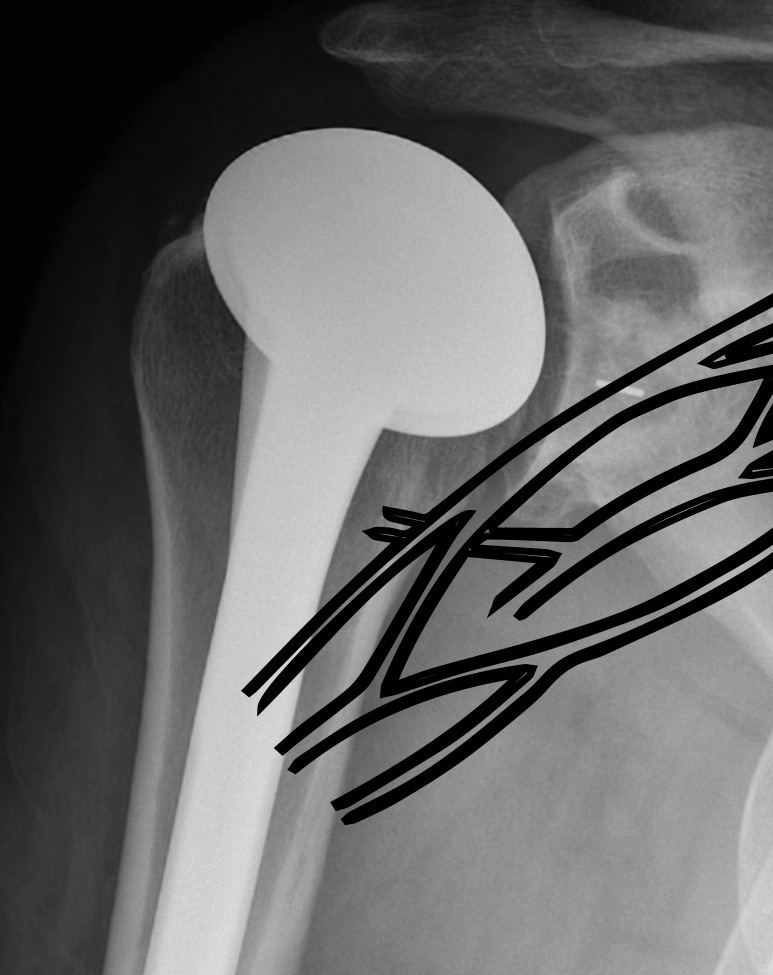

Hum shafthum shaftHum shaft

Stable humeral component treated with ORIF

hum #Hum #Hum #

Unstable humeral component